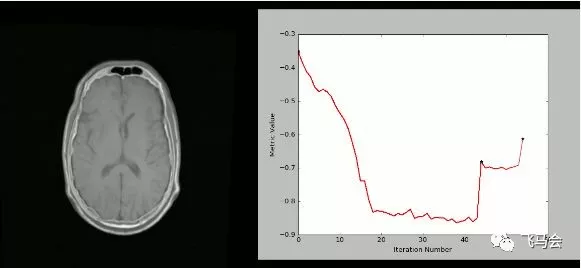

8. SimpleITK

ITK(Insight Segmentation and Registration Toolkit)是一个“开源,跨平台系统,为开发人员提供了一套用于图像分析的广泛软件工具。SimpleITK是一个基于ITK构建的简化层,旨在促进其在快速原型设计,交易以及解释语言方面的应用。”它也是一个图像分析工具包,具有大量组件,支持一般过滤操作,图像分割和配准。SimpleITK是用C ++编写的,但它可用包括Python在内的大量编程语言进行操作。

有大量的Jupyter Notebook说明了SimpleITK在教育和研究活动中的应用。Notebooks使用Python和R编程语言演示如何使用SimpleITK进行交互式图像分析。

用法

使用SimpleITK和Python创建可视化的严格CT / MR配准过程: